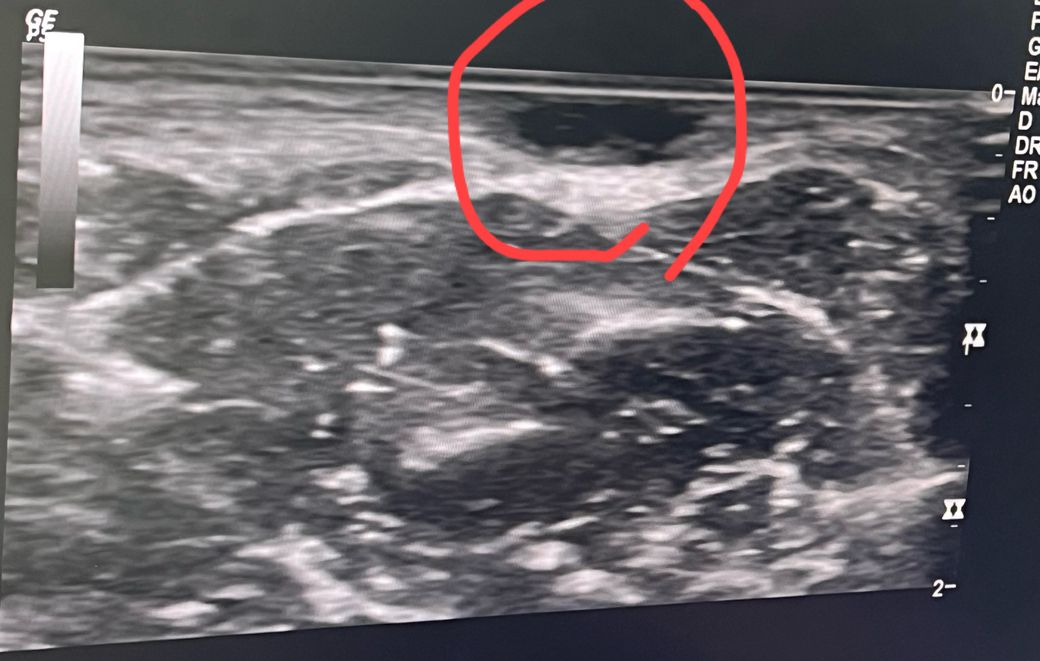

사타구니에 통증없는 멍울이 잡혀 외과에 가서 초음파를 찍고 왔는데, 표피낭종이라고 하더라구요

근데 모양이 불규칙해서 걱정이되네요,, 불규칙 하면 악성일 가능성이 있다고 들어서요,,,

병원에서는 단순 표피낭종이라고 하셨는데 다른 의견 있으신가요

내부에 특별히 뭔가 차있는 형태는 아니기 때문에 낭종의 가능성이 크며 악성의 가능성은 높아보이지는 않습니다.

하지만 정확한 진단은 제거를 하시면서 조직검사 까지 받아보시는 것이 좋겠습니다.